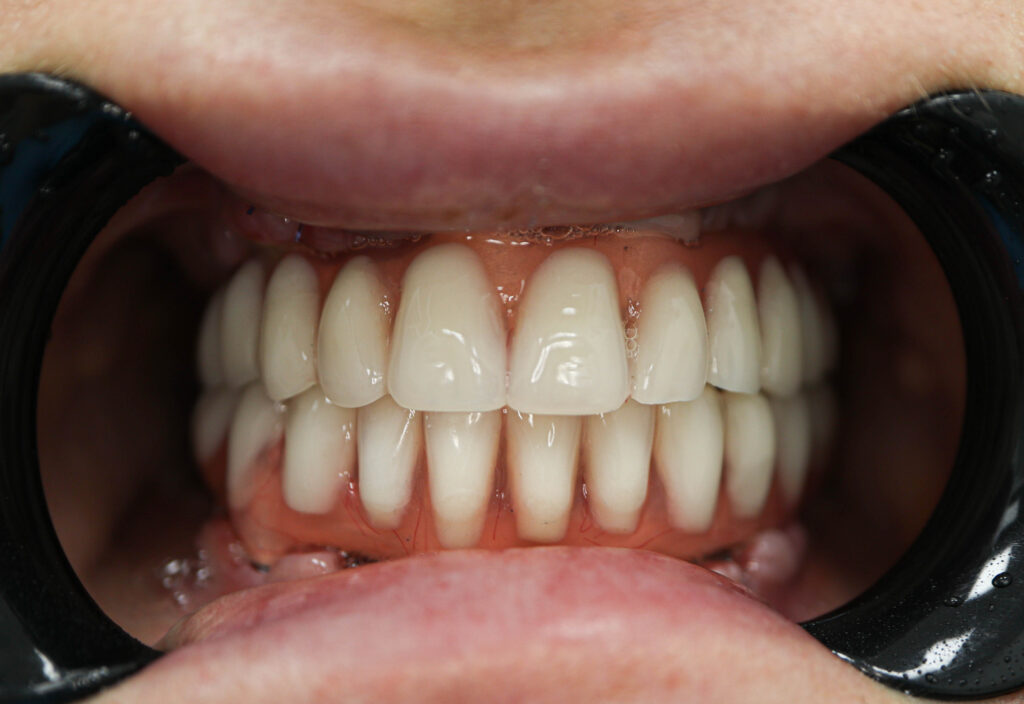

Результаты

Установка 6 классических имплантатов NeoDent и 3 скуловых имплантата